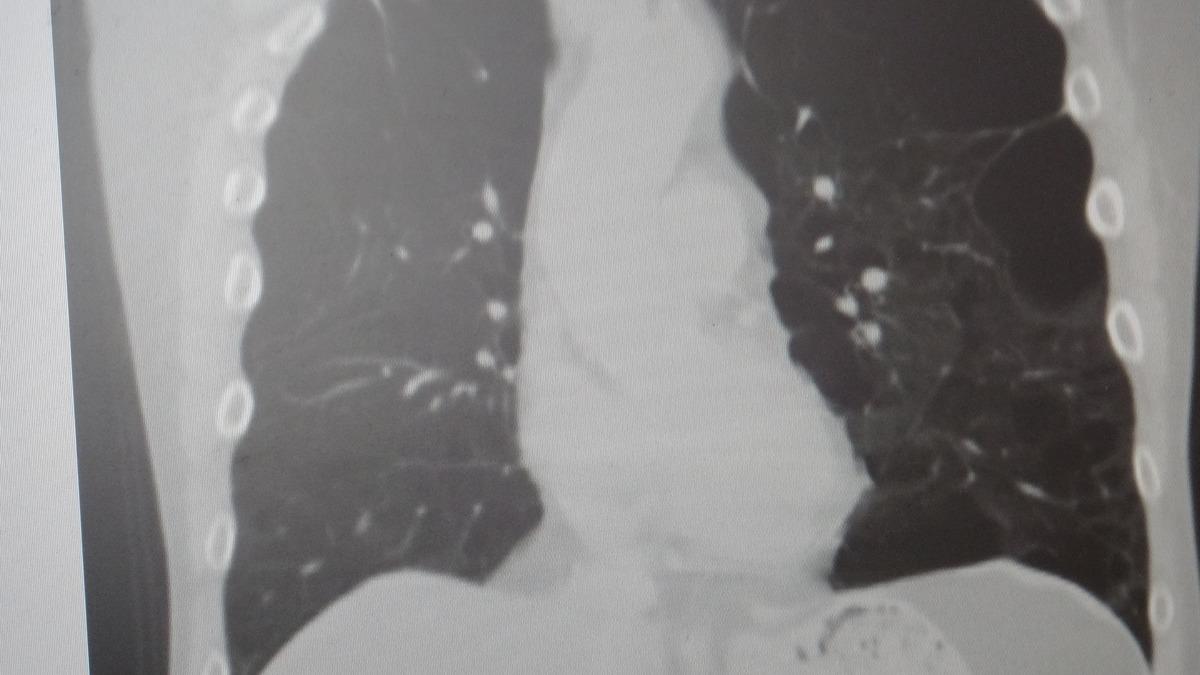

Marmara Üniversitesi Pendik Eğitim ve Araştırma Hastanesi uzmanlarından Prof. Dr. Sait Karakurt, dünya genelinde can kayıplarına neden olan hastalıklar arasında 4'üncü sırada yer alan KOAH ve beraberinde getirdiği zatürre riskine karşı önemli açıklamalarda bulundu.

KOAH, zararlı maddelerin akciğeri parçalamasıyla oluşan bir rahatsızlık ve bunun da en önemli nedeni sigara.

"AKCİĞERİ PARÇALIYOR"